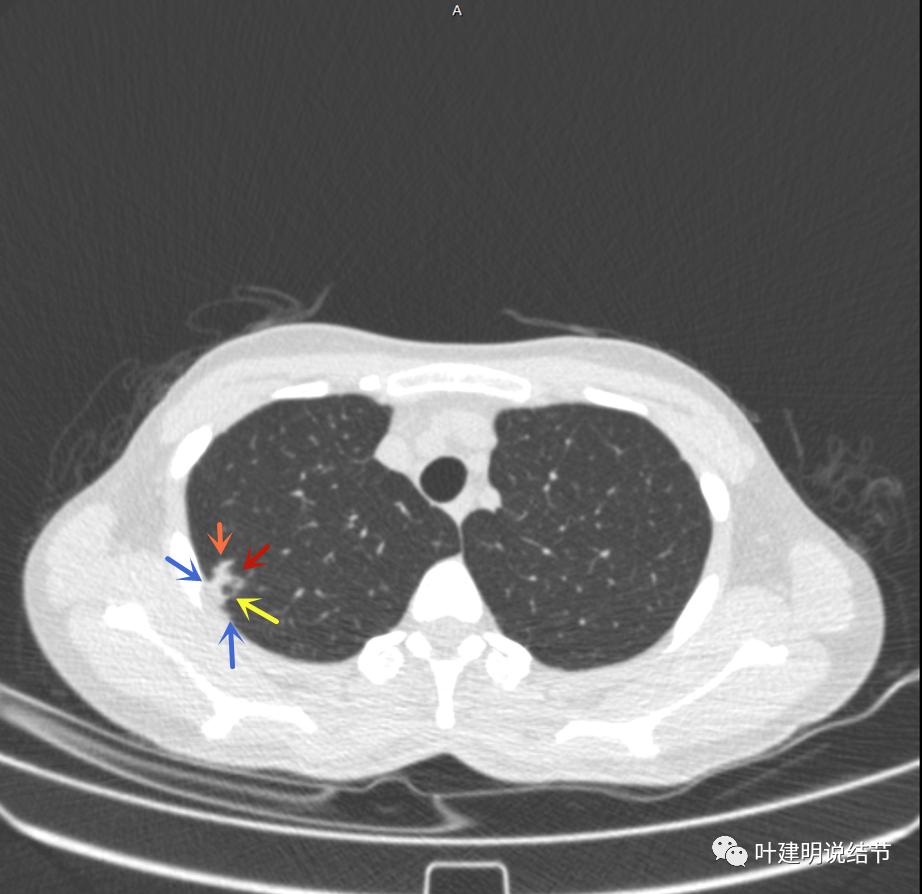

邻近胸膜有增厚(蓝色箭头),主病灶边界较清(红色箭头),实性部分密度过高(粉色箭头),旁边有磨玻璃影,散且模糊(砖色箭头)

邻近胸膜有增厚(蓝色箭头),主病灶实性部分密度过高(粉色箭头),旁边有磨玻璃影,散且模糊(砖色箭头)

邻近胸膜有增厚(蓝色箭头),主病灶实性部分密度过高(粉色箭头),旁边有磨玻璃影,散且模糊(砖色箭头),病灶有空腔(黄色箭头)